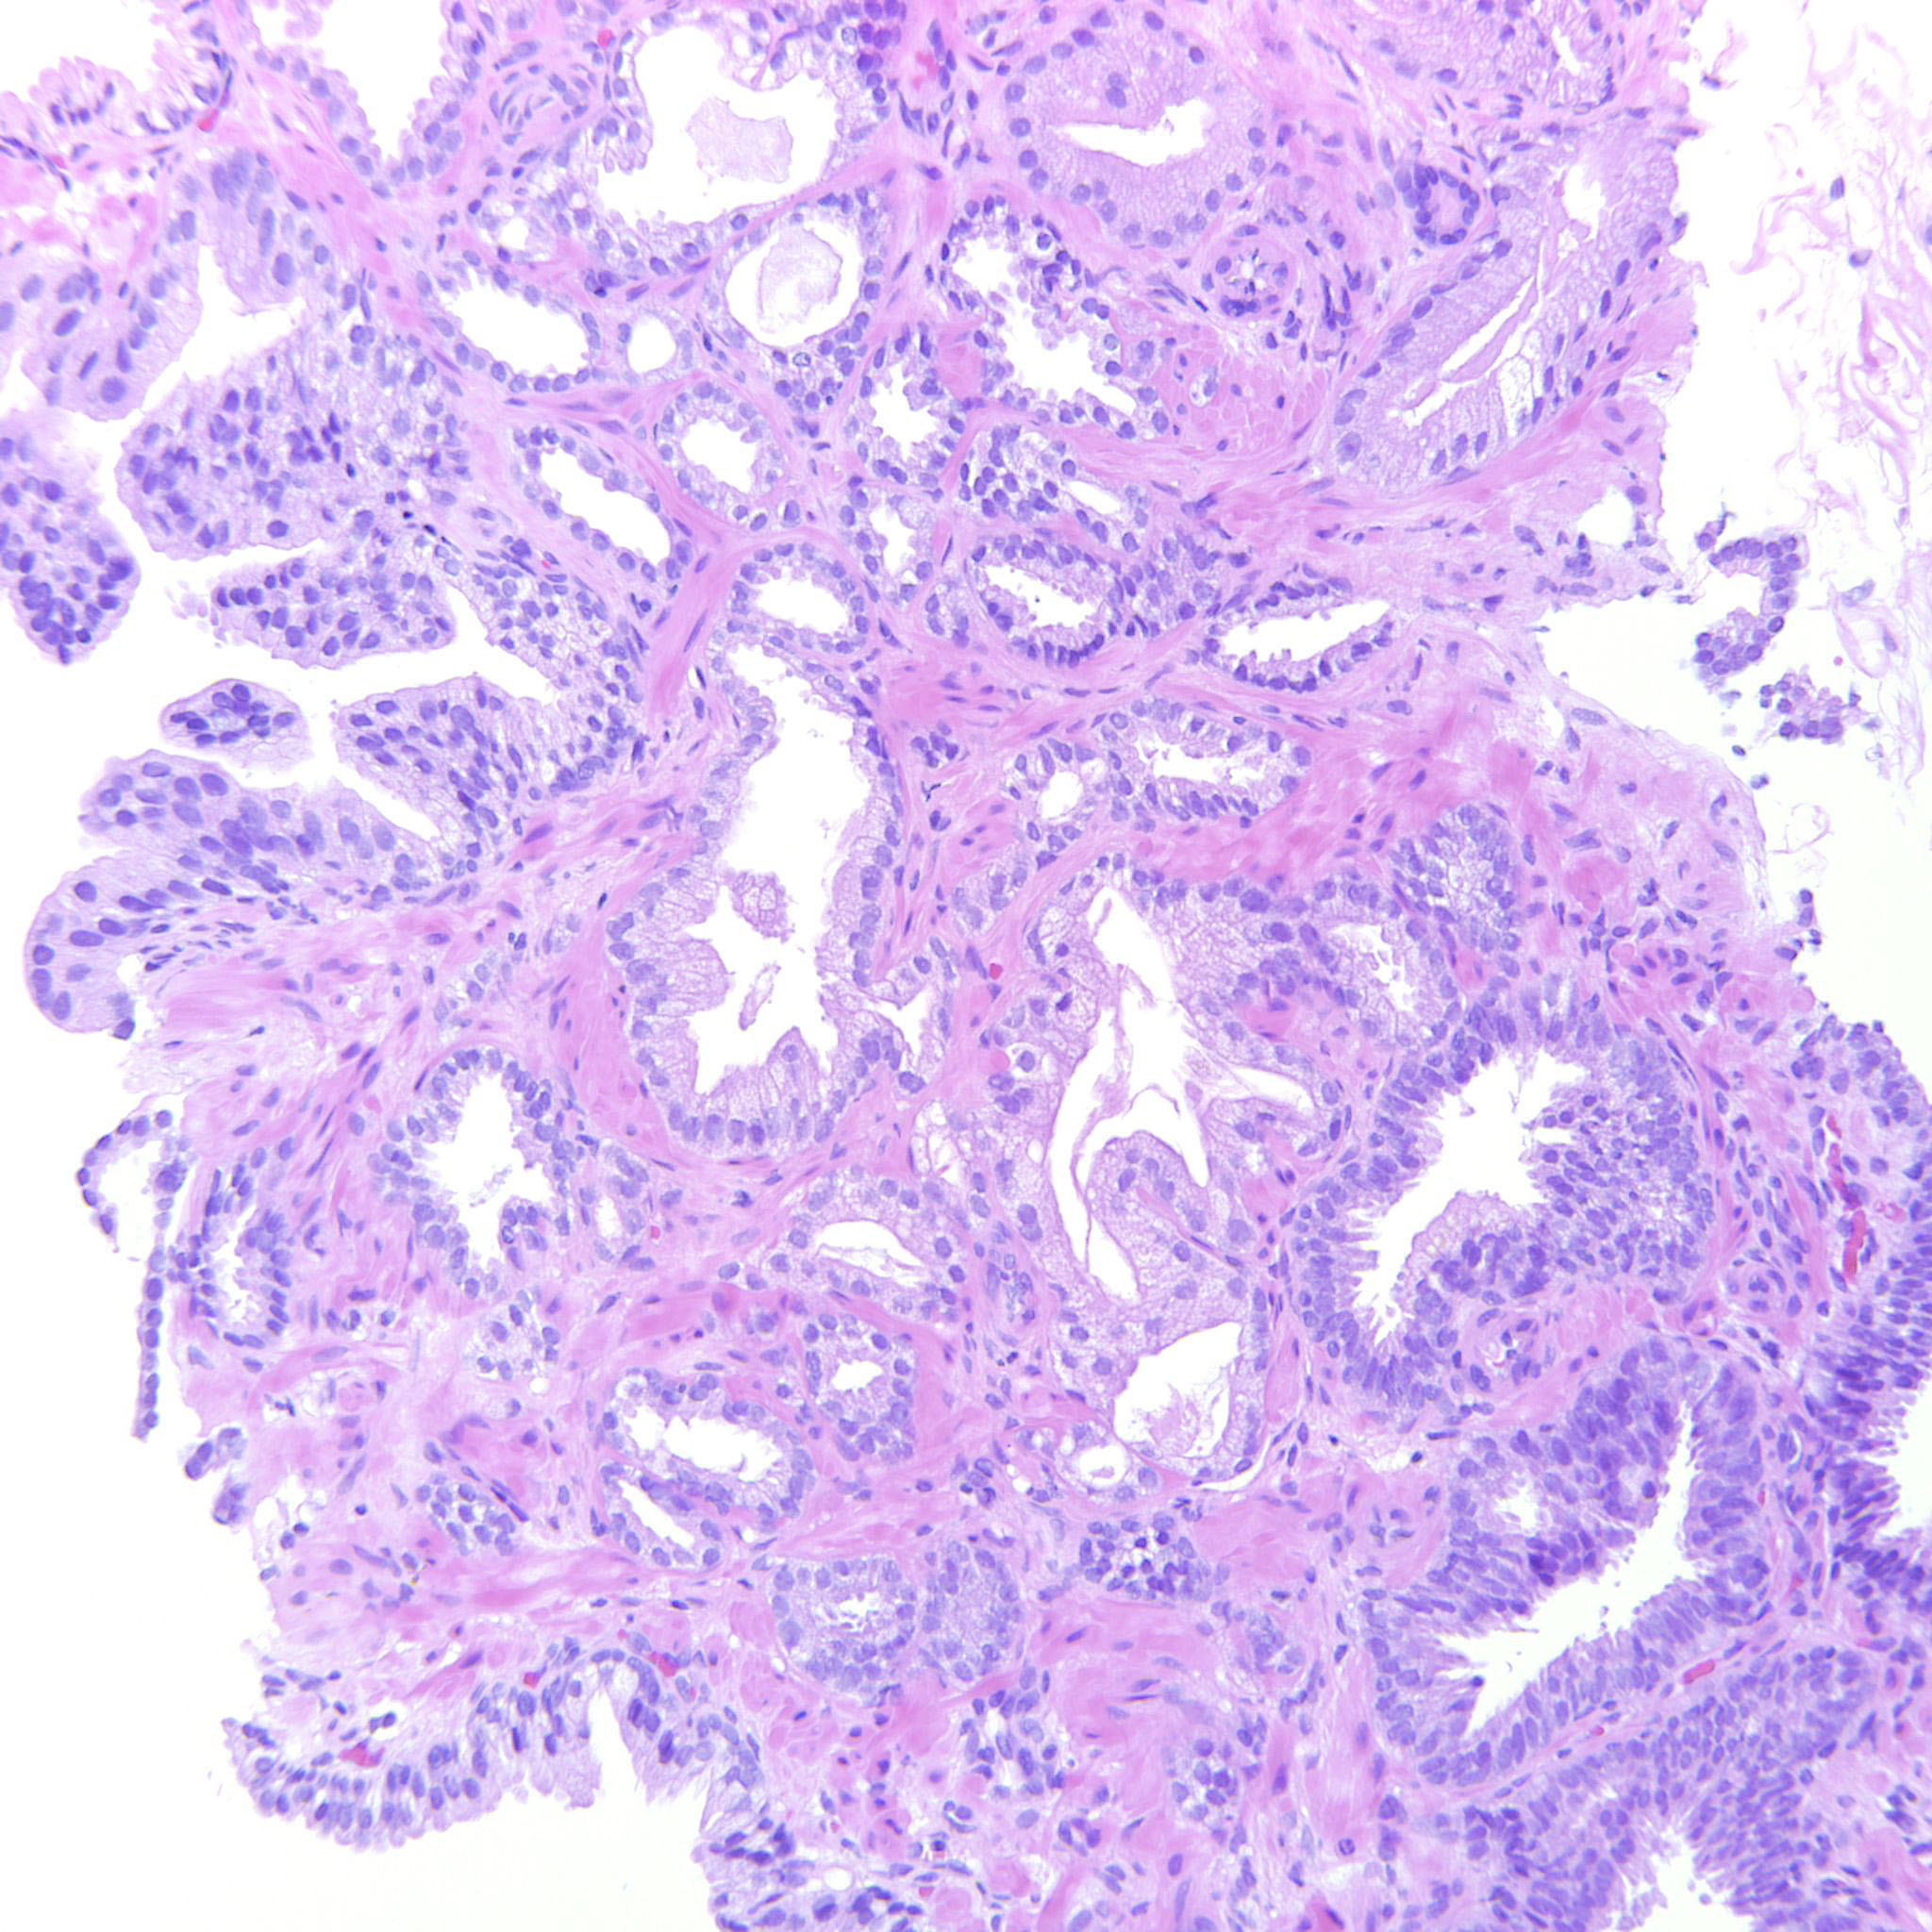

Prostate cancer grading

Case ID: 289